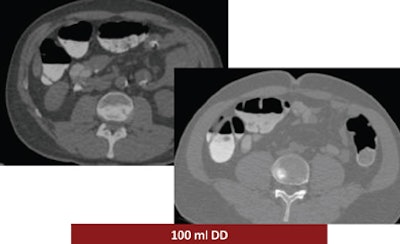

The study looked at three groups of 30 patients who underwent virtual colonoscopy after a same-day bowel preparation. Group 1 ingested 200 mL of undiluted DD the day of the exam, group 2 drank 100 mL of the agent the day of the exam, and group 3 ingested a low-dose polyethylene glycol (PEG) formula (macrogol) the two days before the exam, followed by 100 mL of DD the day of the exam.

According to the results, the mean segment quality values were 2.8 in patient group 1, 2.6 in group 2, and 3.2 in group 3.

"We had the best results in group 1, group 3 had the medium result, and group 2 had the worst results," he said. "The main difference was in the cecum," which produced a mean quality score of 2.3 for group 1, 1.6 for group 2, and 3 for group 3.

Group 1 had the best-quality results, with well-marked colonic mucosa but significant residual fluid. The use of 100 mL DD combined with low-dose polyethylene glycol over two days may have improved fecal tagging by softening the stool before the ingestion of the iodinated agent. In addition, no side effects were reported among the patients who ingested the PEG preparation for two days before the exam (group 3), Ferrari said.

| Above, the use of 200 mL DD in group 1 yielded the highest quality scores. While the colonic mucosa was well marked, significant volumes of fluid remained in the colon, similar to the 100 mL DD preparation (group 2, below). The use of 100 mL combined with low-dose polyethylene glycol over two days (bottom image) may have improved fecal tagging by softening the stool before the ingestion of DD. |